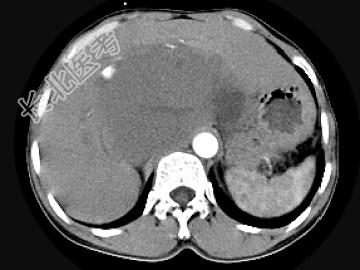

- 单项选择题女,48岁, 中上腹不适,CT扫描如图, 最可能的诊断为 ( )

A、原发性肝癌

B、胆管细胞癌

C、肝血管内皮瘤

D、肝血管瘤

E、小肠间质瘤